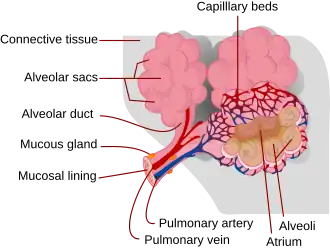

Respiratory zone

The conducting zone of the respiratory tract ends at the terminal bronchioles when they branch into the respiratory bronchioles. This marks the beginning of the terminal respiratory unit called the acinus which includes the respiratory bronchioles, the alveolar ducts, alveolar sacs, and alveoli.[27] An acinus measures up to 10 mm in diameter.[28] A primary pulmonary lobule is the part of the lung distal to the respiratory bronchiole.[29] Thus, it includes the alveolar ducts, sacs, and alveoli but not the respiratory bronchioles.[30]

The unit described as the secondary pulmonary lobule is the lobule most referred to as the pulmonary lobule or respiratory lobule.[25]: 489 [31] This lobule is a discrete unit that is the smallest component of the lung that can be seen without aid.[29] The secondary pulmonary lobule is likely to be made up of between 30 and 50 primary lobules.[30] The lobule is supplied by a terminal bronchiole that branches into respiratory bronchioles. The respiratory bronchioles supply the alveoli in each acinus and is accompanied by a pulmonary artery branch. Each lobule is enclosed by an interlobular septum. Each acinus is incompletely separated by an intralobular septum.[28]

The respiratory bronchiole gives rise to the alveolar ducts that lead to the alveolar sacs, which contain two or more alveoli.[20] The walls of the alveoli are extremely thin allowing a fast rate of diffusion. The alveoli have interconnecting small air passages in their walls known as the pores of Kohn.[20]